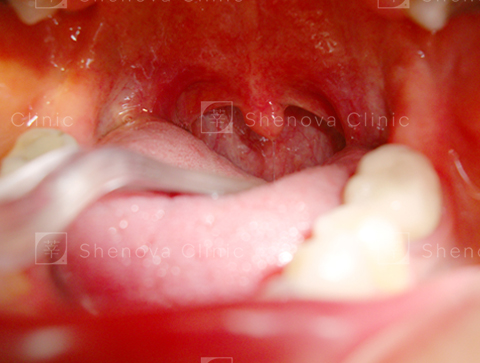

第一級_軟硬顎、扁桃腺、懸壅垂位置圖02

等級一

可見扁桃腺、軟顎、部分懸壅垂。